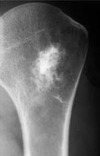

3

Encondroma